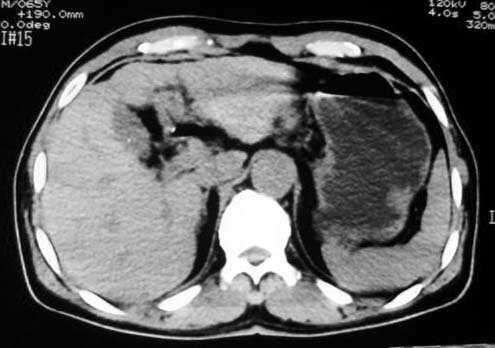

考虑胃的肿瘤或胰尾肿瘤,肝右叶后下段低密占位警惕转移。建议增强检查

从这些图像上看,此软组织团块影,在胃腔的外面,胃壁是一种受压的改变,所以考虑此病灶和胃没有关系,建议进一步增强ct检查。

病灶起源于胃壁向腔内外突出,边缘光整,内可见片状低密度区,考虑胃壁非上皮性肿瘤可能性大

病灶起源于胃壁向腔内外突出,边缘光整,内可见片状低密度区,考虑间质瘤可能性大,建议增强扫描。